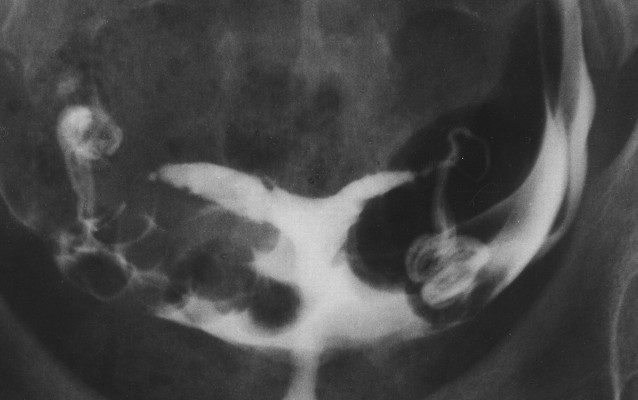

Şekil 1C . Didelfis

Çift rahim boşluğu sıklıkla ilk kez histerosalpingografi sırasında tespit edilir; bu test, 80 yılı aşkın süredir doğurganlık sorunu olan çiftlerin değerlendirilmesinde temel dayanak noktası olmuştur. Spesifik müllerian anomalinin doğru tanısı, genellikle standart histerosalpingografi ile sağlanamayan dış uterus fundus konturunun (Şekil 1A , 1B , 1C , 1D , 1E , 1F , 1G ) görüntülenmesini gerektirir.

Histerosalpingografideki bulgular spesifik müllerian anomaliyi düşündürebilir. Eğer iki uterus boşluğu geniş aralıklıysa ve aralarında 105°’den büyük bir açı varsa, uterusun septattan ziyade bikornuat veya didelfis olma olasılığı daha yüksektir. Ancak bu güvenilir bir bulgu değildir ve cerrahi düzeltmeden önce tanıyı doğrulamak için sonografi, MR görüntüleme ve laparoskopi gibi ek çalışmalara ihtiyaç duyulmuştur.